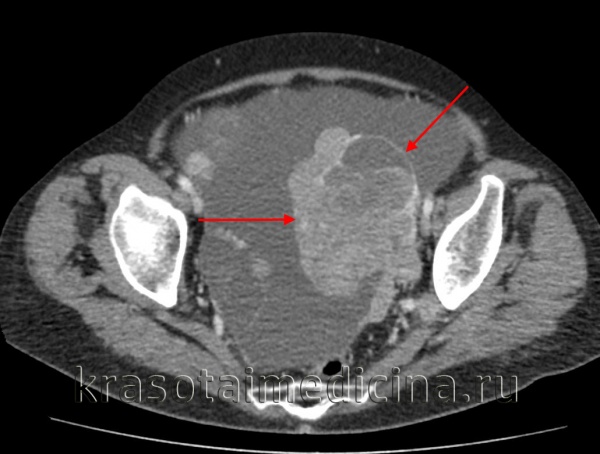

КТ живота и таза. Массивное объемное образование яичника с гиповаскулярным центром (красная стрелка), гиперваскулярной периферией (зеленая стрелка) и включениями газа (синяя стрелка). Гистологически подтвержденная гранулезоклеточная опухоль яичника.